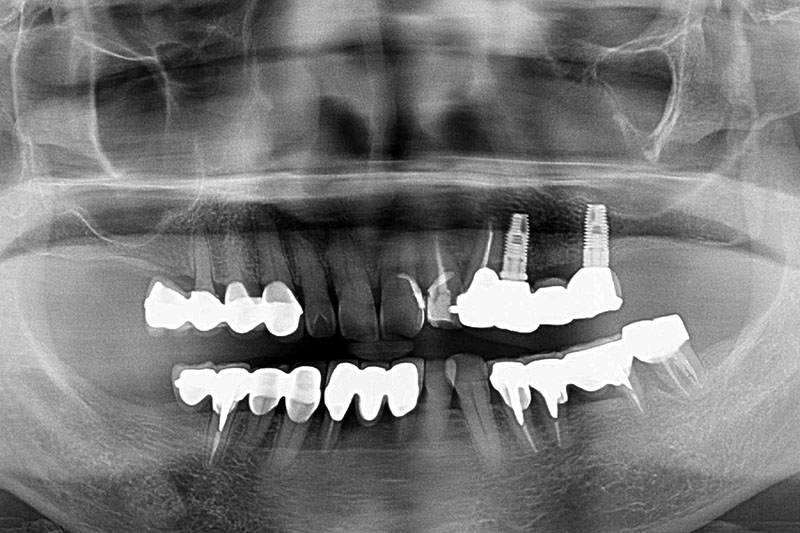

缺牙多顆-全口X光攝影

案例一

術前

術後